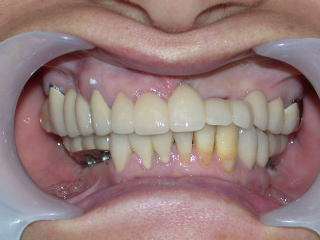

入れ歯で充分な満足が得られない場合はインプラント(人工歯根)を植立してその上に冠をかぶせます。

歯の抜けた部分に人工歯根を植立し、その上に土台を入れ、その上に白い歯を被せます。

1枚目写真はインプラントの例です。

2枚目写真以降ブリッジの例です。